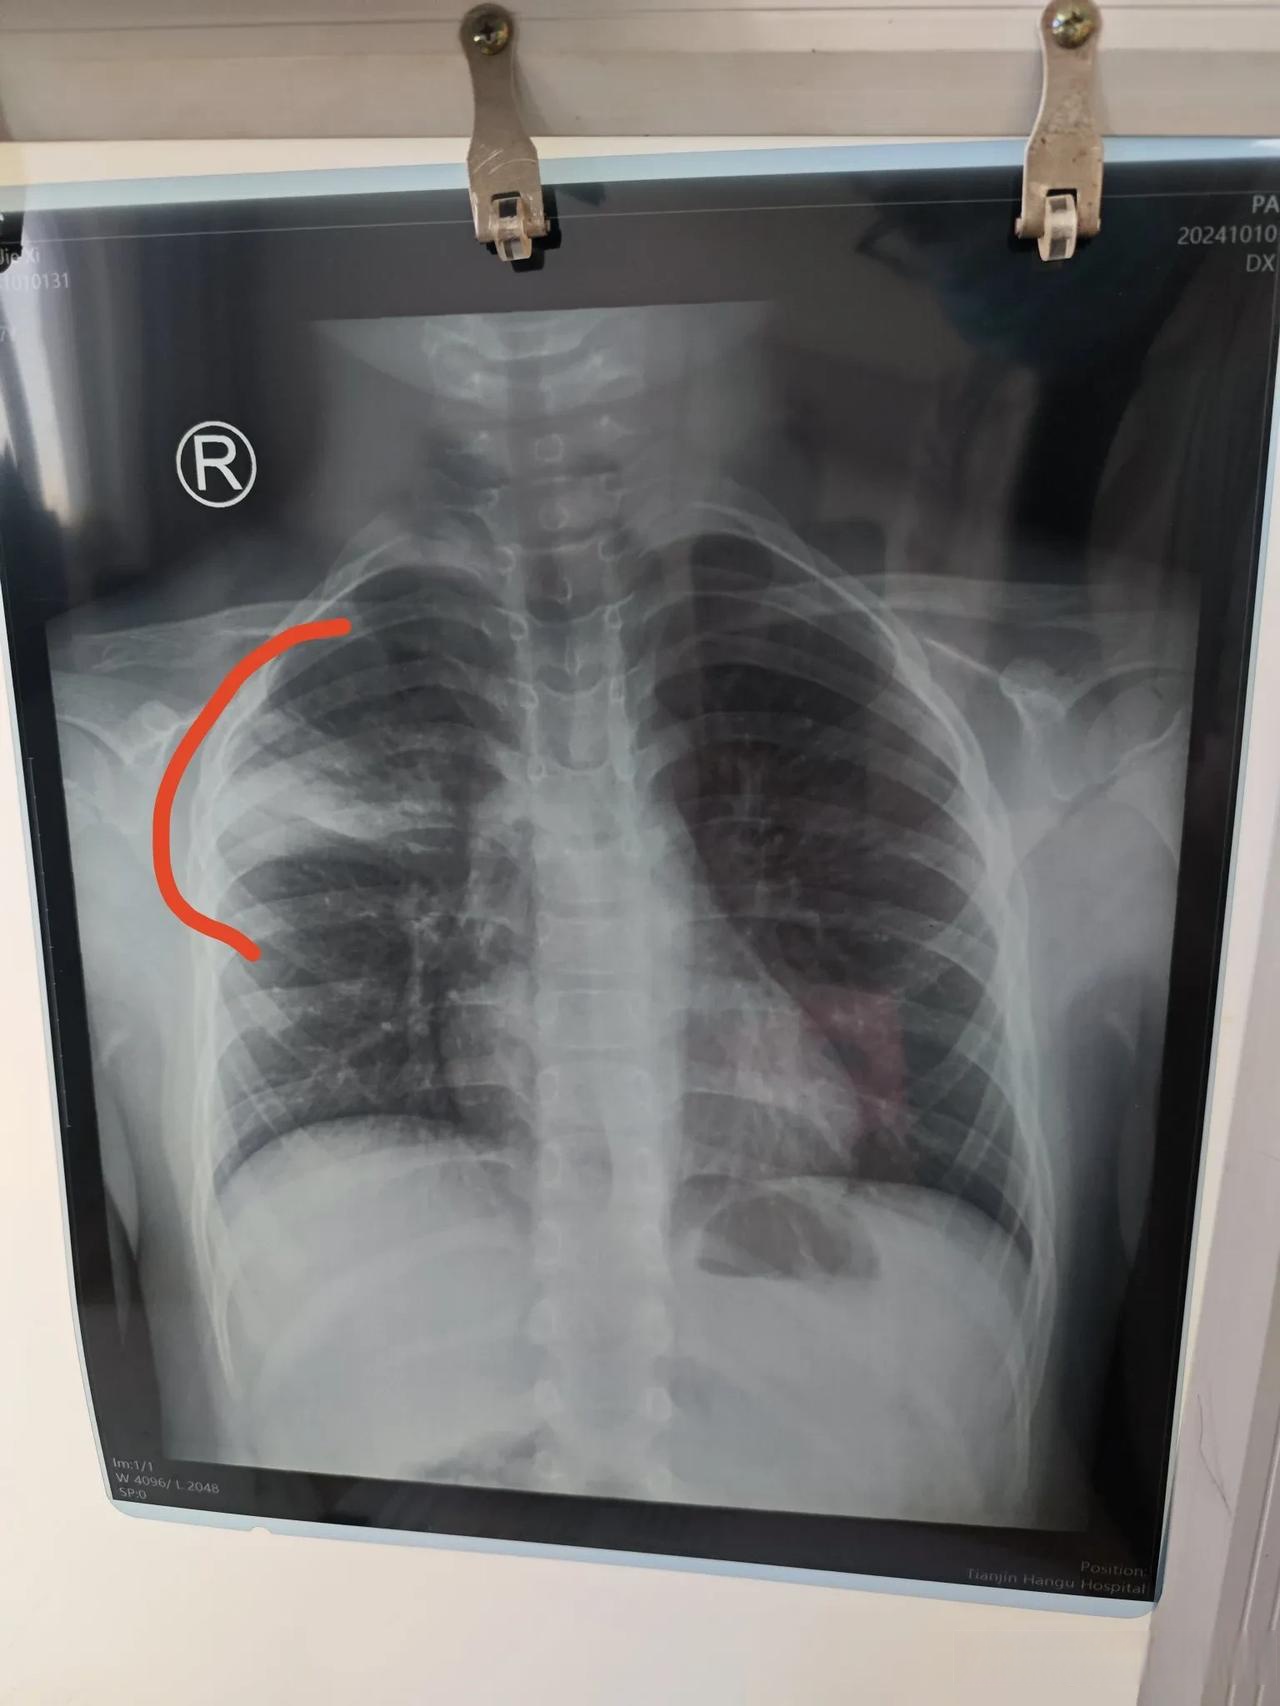

大叶性肺炎,顾名思义,是肺部的一个或多个大叶(肺由多个肺叶组成)被炎症所侵袭。它通常由细菌感染引起,其中肺炎链球菌是最常见的元凶。这种疾病的临床表现典型且剧烈,如同一场在肺部上演的激烈“战争”,其过程甚至有着经典的四期病理变化。了解其症状,对于及时就医至关重要。

红色肝样变期(发病第3-4天):

病理: 肺泡内充满大量红细胞和纤维素,肺组织变得坚实如肝脏,故称“肝样变”。

临床: 典型症状全部显现:稽留热、铁锈色痰、胸膜性胸痛、呼吸困难。体检可见患侧呼吸运动减弱,叩诊呈浊音。